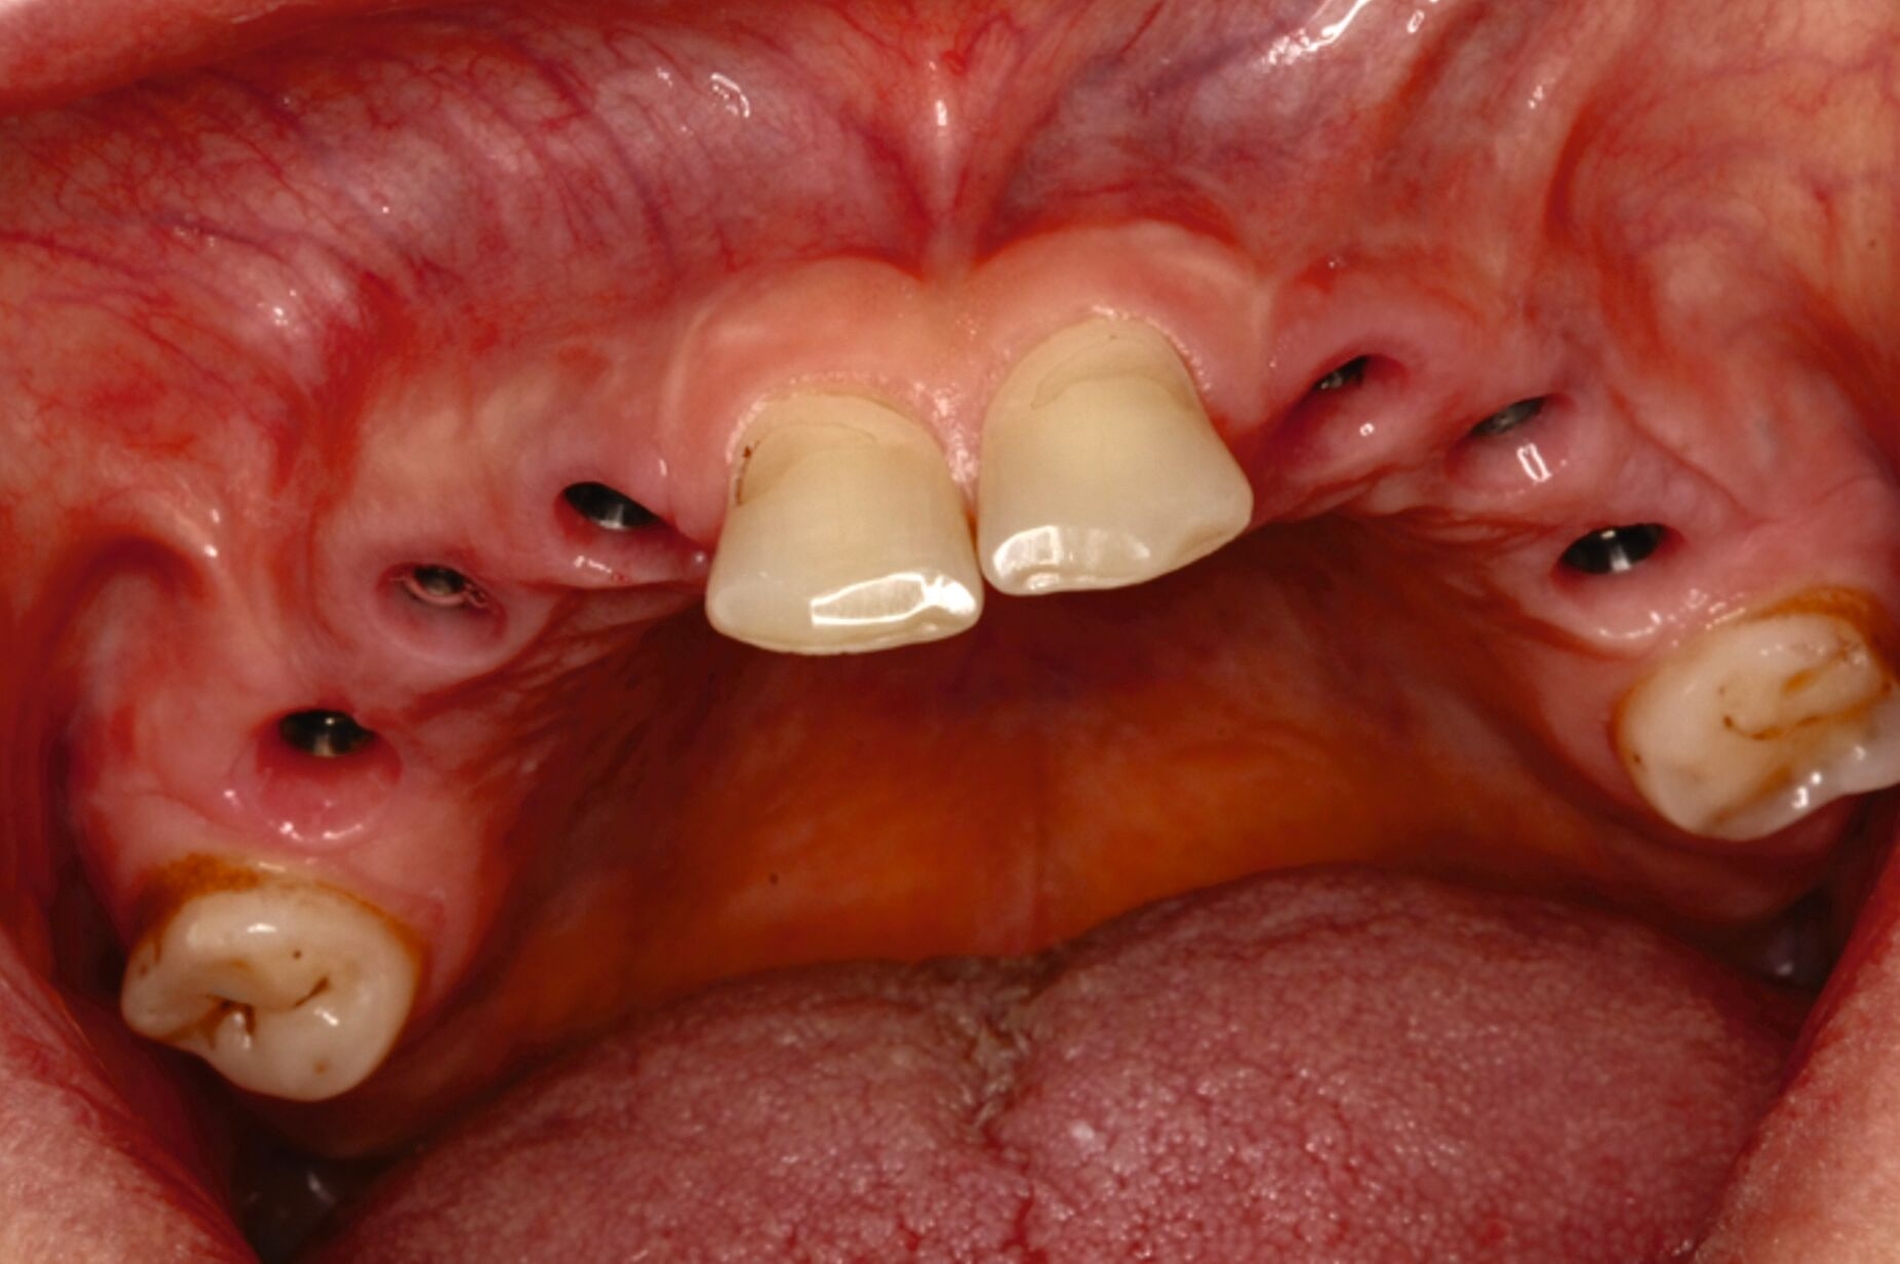

Ein 30-jähriger Patient stellte sich mit multipler Oligodontie (15 fehlende bleibende Zähne), Persistenz von Milchzähnen sowie ausgeprägter Dysgnathie mit progenem Deckbiss vor. Klinisch zeigten sich hypoplastische Restzähne, Fehlstellungen und erhebliche funktionelle Beeinträchtigungen (Abbildung 1). Sein Wunsch bestand in einer möglichst optimalen ästhetischen und funktionellen Versorgung seiner für ihn äußerst unbefriedigenden Gebisssituation. Die molekulargenetische Analyse bestätigte eine homozygote Mutation im WNT10A-Gen als Ursache der Zahnagenesie.